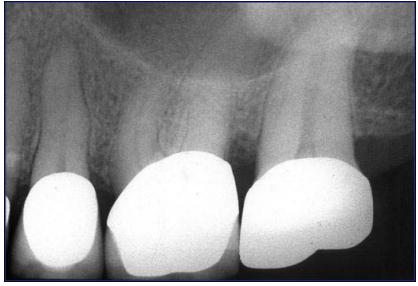

4.李伯伯兩週前上顎左側開始對冷水刺激感到不適,症狀逐漸嚴重故求診,其X光片結果如下圖所 示,對於此症狀的診斷,下列何者正確?

(A)第二小臼齒因牙冠內再度齲齒(recurrent decay),需進行根管治療 (B)第一大臼齒因根管系統鈣化,需進行根管治療 (C)第二大臼齒因根管內吸收,需進行根管治療 (D)無法由此X光片判斷何者需根管治療